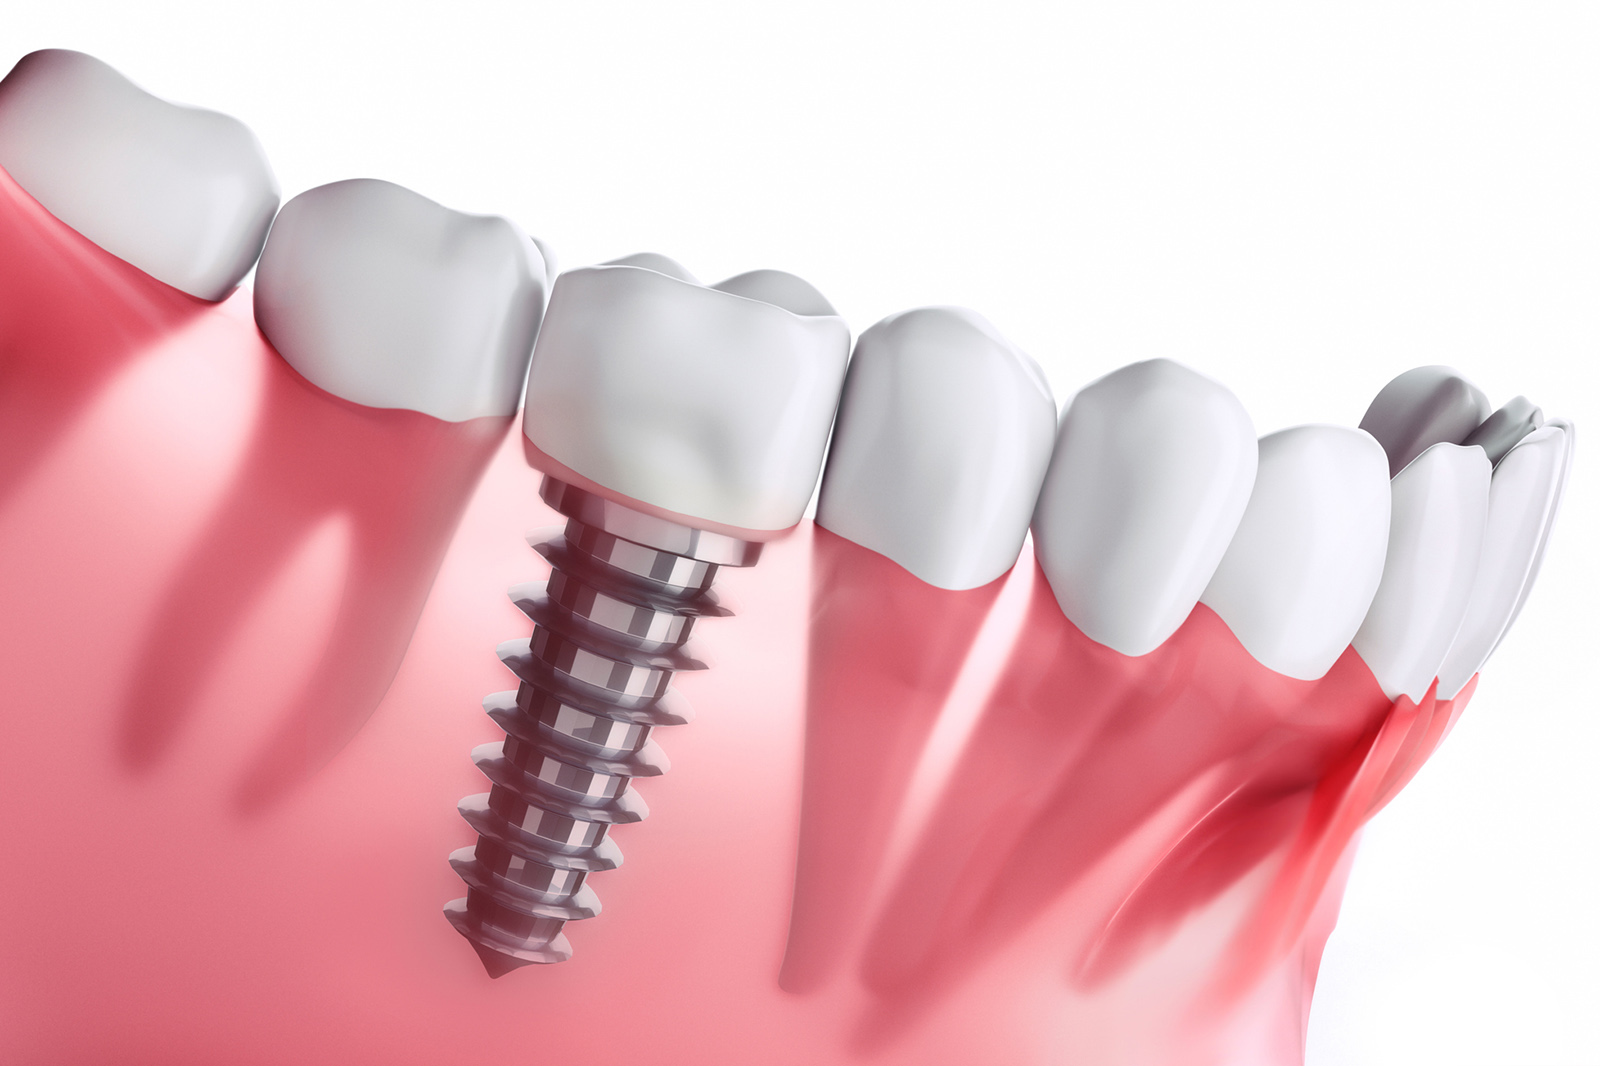

これ以上歯を失わないための治療、

それがインプラントです。

意外に知られていない事実として、インプラント治療は「健康な歯に影響を与えない唯一の治療法」であることが挙げられます。インプラントは他の歯に依存せず、独立して機能するため、周囲の歯に悪影響を及ぼしません。

さらに、インプラントはブリッジや入れ歯と比較して「噛む力」や「耐用年数」において多くの利点があります。